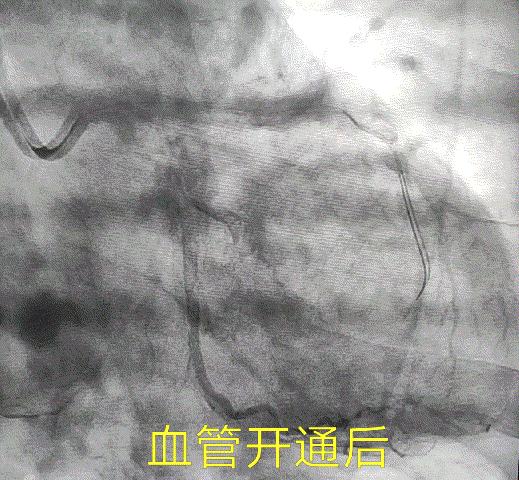

急诊时,张健医生团队紧急为老范开通了罪犯血管,狭窄的前降支和回旋支血管。

开通完血管后的一个多月来,老范说他再也没出现过嗓子冒烟的症状。